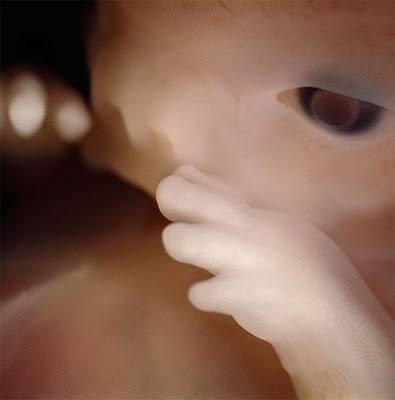

Պտուղն արդեն 16 շաբաթական է:

16 շաբաթական պտուղն սկսում է օգտագործել ձեռքերը, որպեսզի ուսումնասիրի սեփական մարմինը: